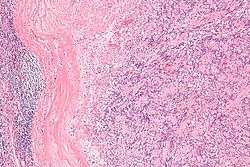

| Micrograph of an intranodal palisaded myofibroblastoma. H&E stain. | |

They have a rim of peripheral lymphoid tissue (remnant of a lymph node) and consist of spindle cells with nuclear palisading. Red blood cell extravasation is common and blood vessels surrounded by collagen with (fine) peripheral spokes (amianthoid fibers) are usually seen.[2]

Immunostains for smooth muscle actin and cyclin D1 are characteristically positive. The main histologic differential diagnosis is schwannoma.

Low mag.

Low mag. High mag.